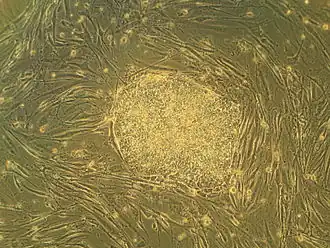

Human embryonic stem cells in cell culture

Embryonic stem cells (ESCs) are pluripotent stem cells derived from the inner cell mass of a blastocyst, an early-stage pre-implantation embryo.[1][2] Human embryos reach the blastocyst stage 4–5 days post fertilization, at which time they consist of 50–150 cells. Isolating the inner cell mass (embryoblast) using immunosurgery results in destruction of the blastocyst, a process which raises ethical issues, including whether or not embryos at the pre-implantation stage have the same moral considerations as embryos in the post-implantation stage of development.[3][4]